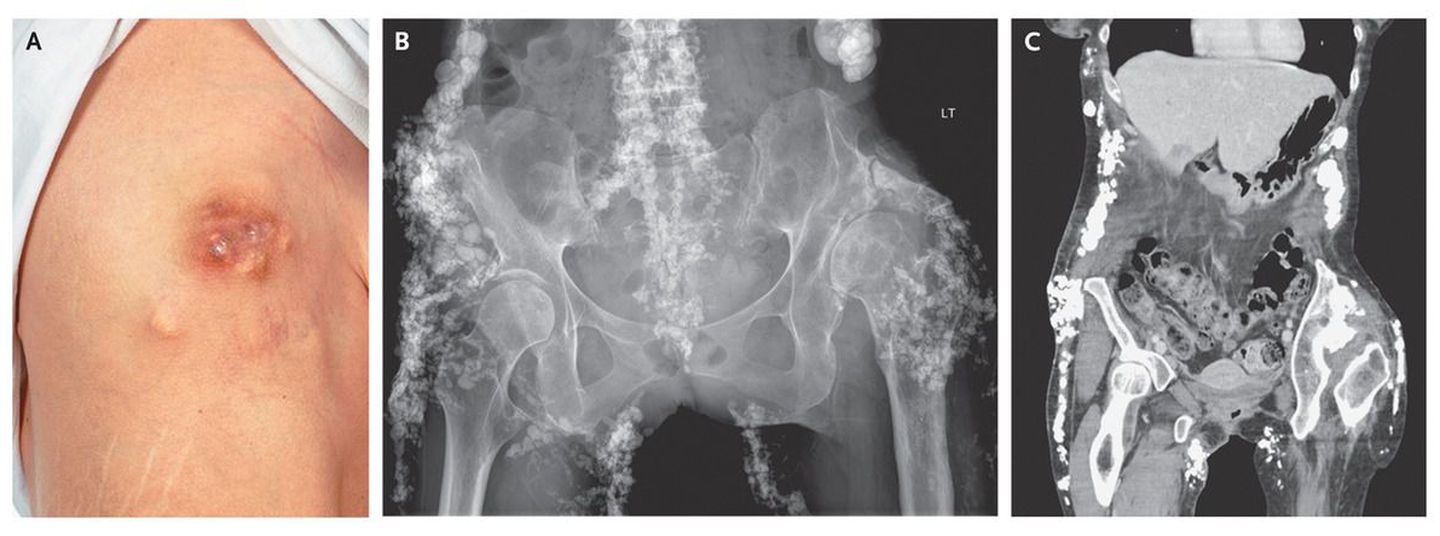

A 41-year-old woman received a diagnosis in 2000 of an overlap syndrome, with limited systemic sclerosis and dermatomyositis. Subcutaneous hard lumps developed over her buttocks and elbows in 2001 and progressed clinically (shown on the inferior axillary area of the right chest wall in Panel A) and radiographically (Panels B and C). The biggest lesions were subsequently excised, but they reappeared within 1 year after surgery. Histologic examination revealed calcified deposits in subcutaneous fibrofatty tissue, findings consistent with a diagnosis of calcinosis cutis. Calcinosis cutis has been reported in cases of systemic sclerosis, dermatomyositis, and mixed connective-tissue disorders. The condition causes substantial complications and can be difficult to treat. Since diagnosis, the patient's treatment has included glucocorticoids, azathioprine, and methotrexate for the connective-tissue disorder and, more specifically, bisphosphonates and minocycline for calcinosis cutis. Despite treatment, the patient has persistent, extensive calcification over her buttocks, shins, and forearms, with recurrent infections at calcified sites.